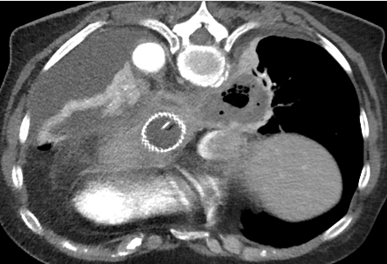

Cas 1 : Femme de 64 ans, transférée pour complication post fundoplicature de Nissen,

drainage sous scanner d’un abcès médiastinal postérieur droit.